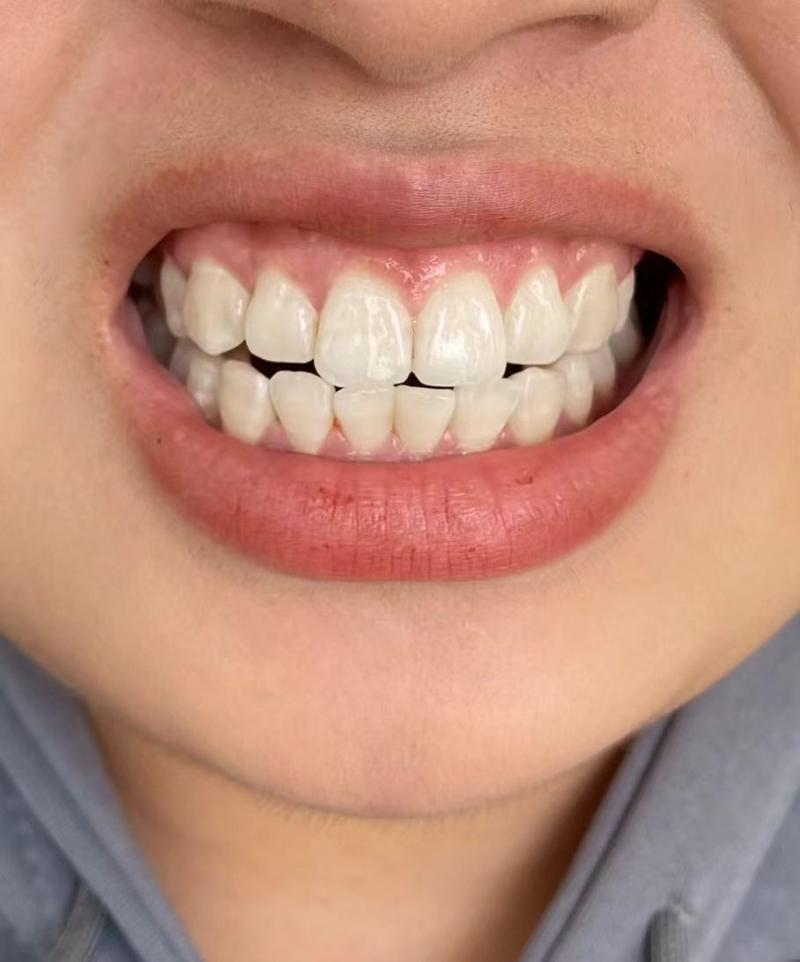

种植体看起来变长或牙龈退缩:

随着牙龈退缩和骨吸收,种植体或基台部分暴露,看起来比之前“长”了。